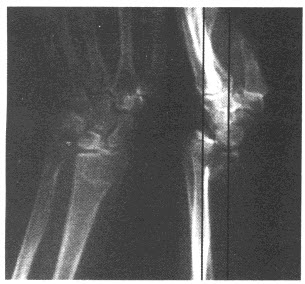

17、单项选择题

男,10岁,左膝关节反复肿胀,伴低热2年,经抗感染效果不佳,结合图像,最可能诊断是()

A.左膝关节结核(滑膜型)

B.左膝关节结核(骨型)

C.左膝关节结核(混合型)

D.左膝化脓性关节炎

E.以上均不正确